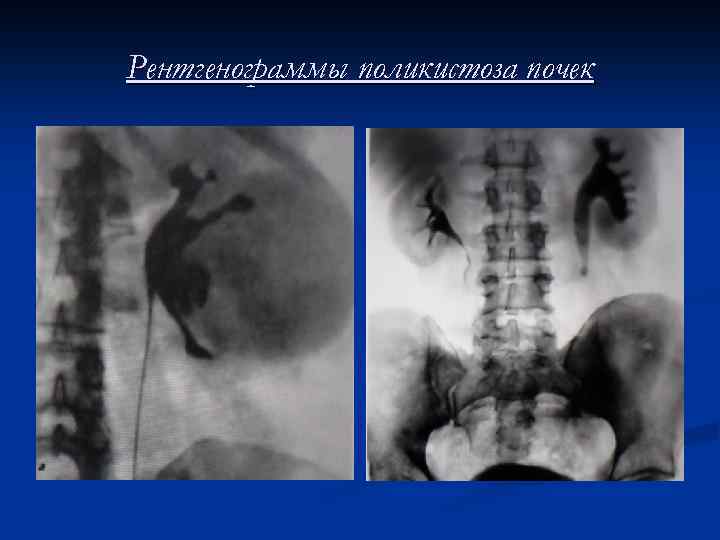

Схема симптомов поликистоза почек 1. 2. 3. 4. 5. 6. 7. 8. 9. 10. 11. 12. 13. 14. 15. 16. Увеличение размеров почки Увеличение лоханочного дерева Расположение нижнего полюса на уровне повздошной кости Расширенные и округленные малые чашечки Расширение чашечек в виде лепестка Удлинение и сужение шейки чашечки Изображение в виде полулуния Изображение в виде клешни рака Симптом розетки Симптом спицы колеса Симптом вставления Ползучие чашечки Изображение в виде конфеты Изображение верхней чашечки в виде конуса

Рентгенограммы поликистоза почек